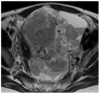

Results: Four qualitative MR features most strongly associated with LMS were nodular borders, haemorrhage, "T2 dark" area(s), and central unenhanced area(s) (p ≤ 0.0001 each feature/reader). The highest sensitivity [1.00 (95%CI:0.82-1.00)/0.95 (95%CI: 0.74-1.00)] and specificity [0.95 (95%CI:0.77-1.00)/1.00 (95%CI:0.85-1.00)] were achieved for R1/R2, respectively, when a lesion had ≥3 of these four features. Sixteen texture features differed significantly between LMS and ALM (p-values: <0.001-0.036). Unsupervised clustering achieved accuracy of 0.75 (sensitivity: 0.70; specificity: 0.79).

Key points: • Four qualitative MR features demonstrated the strongest statistical association with LMS. • Combination of ≥3 these features could accurately differentiate LMS from ALM. • Texture analysis was a feasible semi-automated approach for lesion categorization.